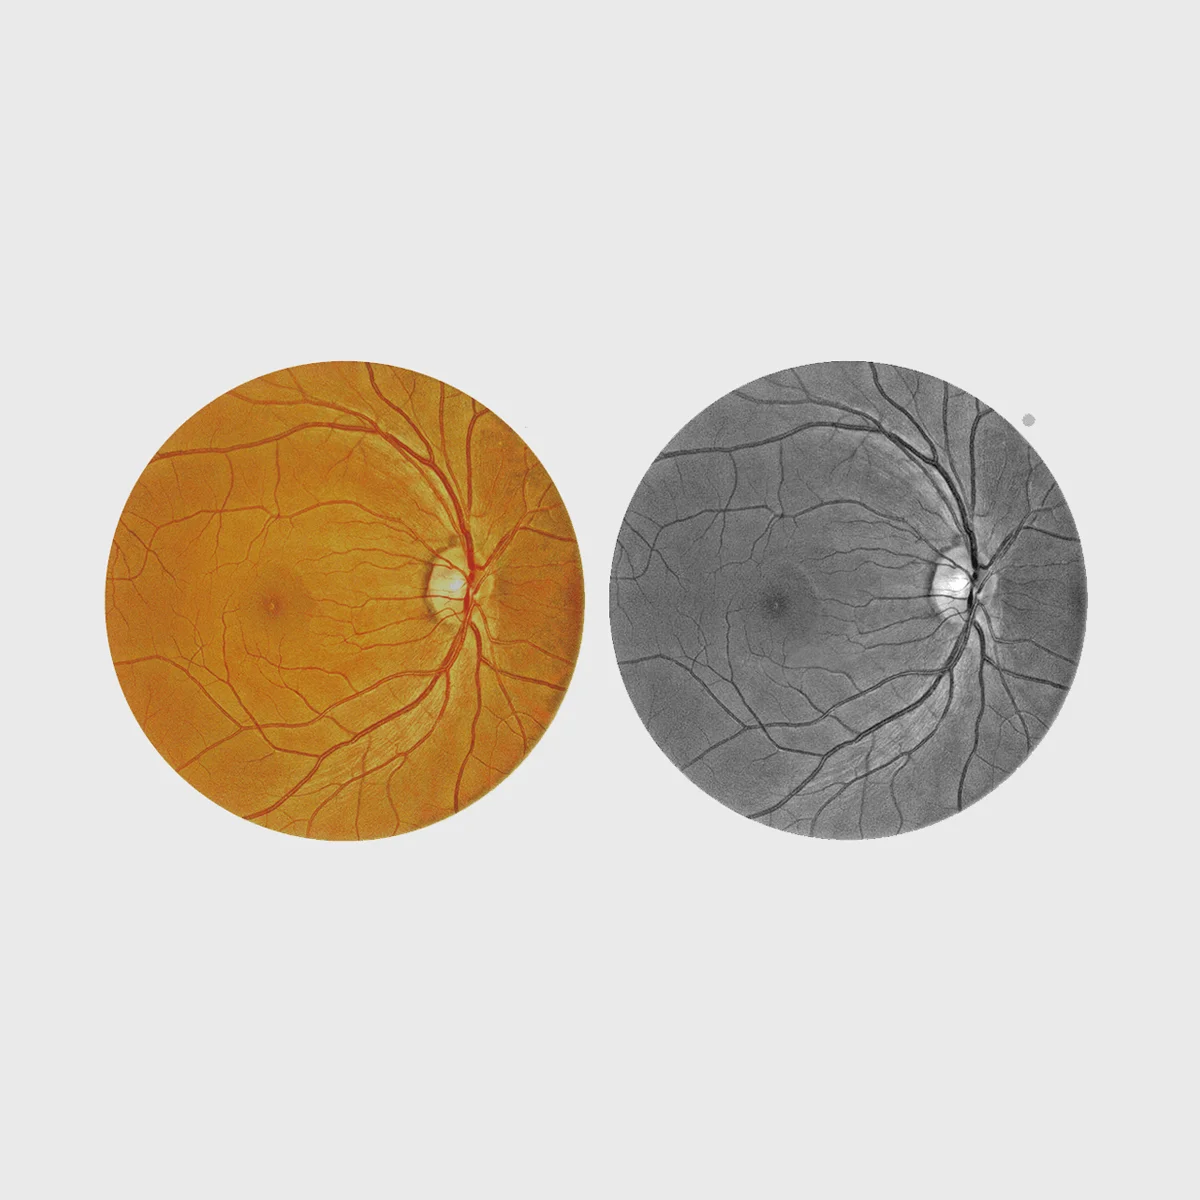

Imagem do fundo do olho a cores

A captura de imagens retinianas a cores de alta resolução e ajustadas ao contraste é inestimável para a análise e o diagnóstico clínico do segmento posterior do olho. Combinámos a baixa intensidade do flash, a velocidade de captação rápida, o funcionamento silencioso, o modo de pupila pequena e a deteção automática de pestanejo para captar as melhores imagens possíveis.